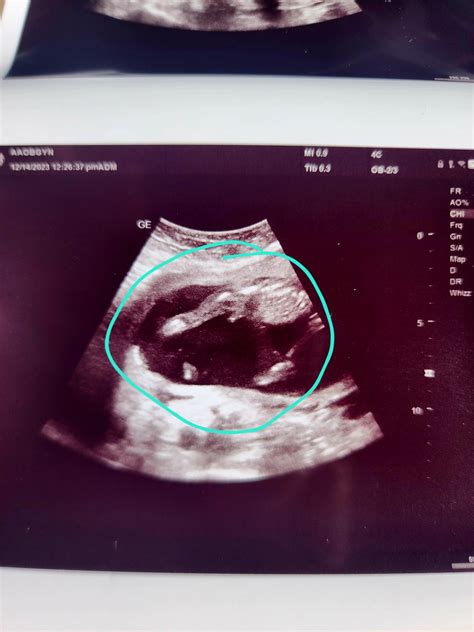

Understanding the Ultrasound Images

The 16 week ultrasound provides detailed images of the baby’s anatomy. Healthcare providers will look for specific features to ensure everything is developing normally. Some of the key areas of focus include:

• Head and Brain: The shape and size of the head, as well as the development of the brain structures.

• Heart: The structure and function of the heart, including the four chambers and major blood vessels.

• Spine: The alignment and development of the spinal column.

• Limbs: The length and structure of the arms and legs, including the hands and feet.

• Abdominal Organs: The development of the stomach, intestines, kidneys, and bladder.